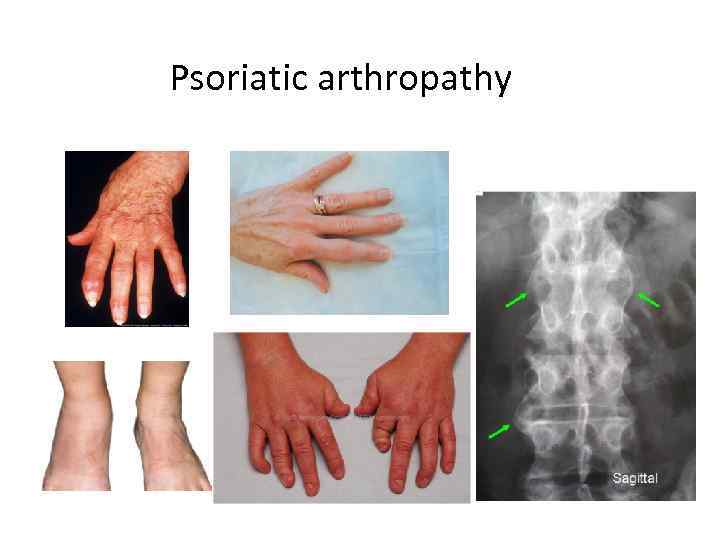

Psoriatic arthropathy

Psoriasis

Enthesopathy